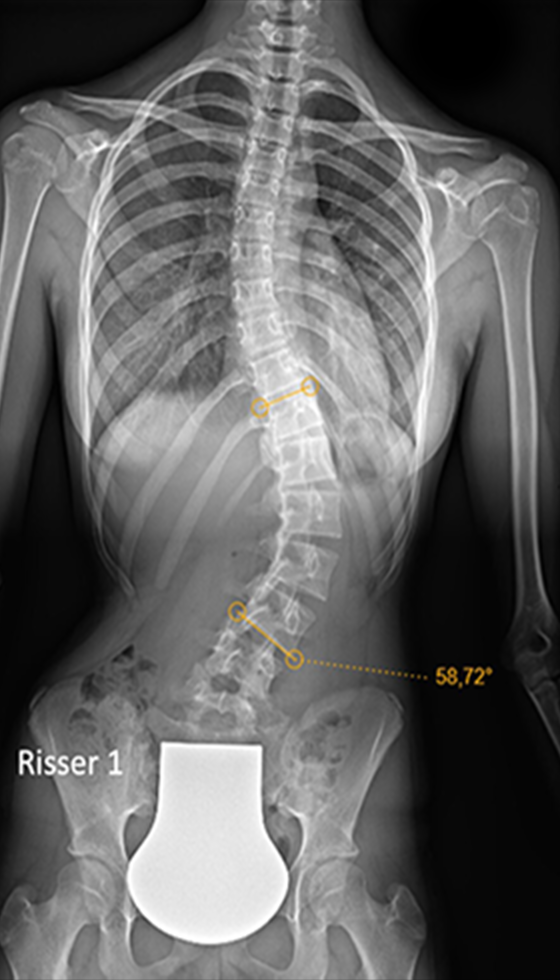

Scoliosis is a common condition characterized by a sideways curvature of the spine, often emerging during puberty. While its origins can vary, most cases are mild. However, without proper attention, severe deformities may lead to significant functional disabilities, impacting lung function and overall well-being.

1. Spinal Fusion (Complex Scoliosis Correction) — Typically Severe / Progressive Curves

Spinal Fusion is the most established surgical option for scoliosis and is commonly recommended for Moderate-to-Severe or Complex Curves, especially when the curve is progressing or affecting balance and function. It is most often considered when curves reach ~45–50° or more in many adolescent cases, and for larger or symptomatic progressive curves in adults (threshold can vary by case).

Typical Cobb-angle ranges (for General Guidance; Individualized by Case) are as follows:

• Fusion Component (for Structural/Rigid Curves): This is often considered when a significant curve measures around 45° to 50° or more, especially if it is progressive, causing imbalance, or affecting the patient's function or appearance.

Gallery : Before - After

After

Before